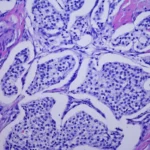

La intoxicación por bloqueadores beta-adrenérgicos es un fenómeno clínico complejo que se asocia a la administración excesiva o inadecuada de fármacos que actúan sobre los receptores beta-adrenérgicos del sistema nervioso…